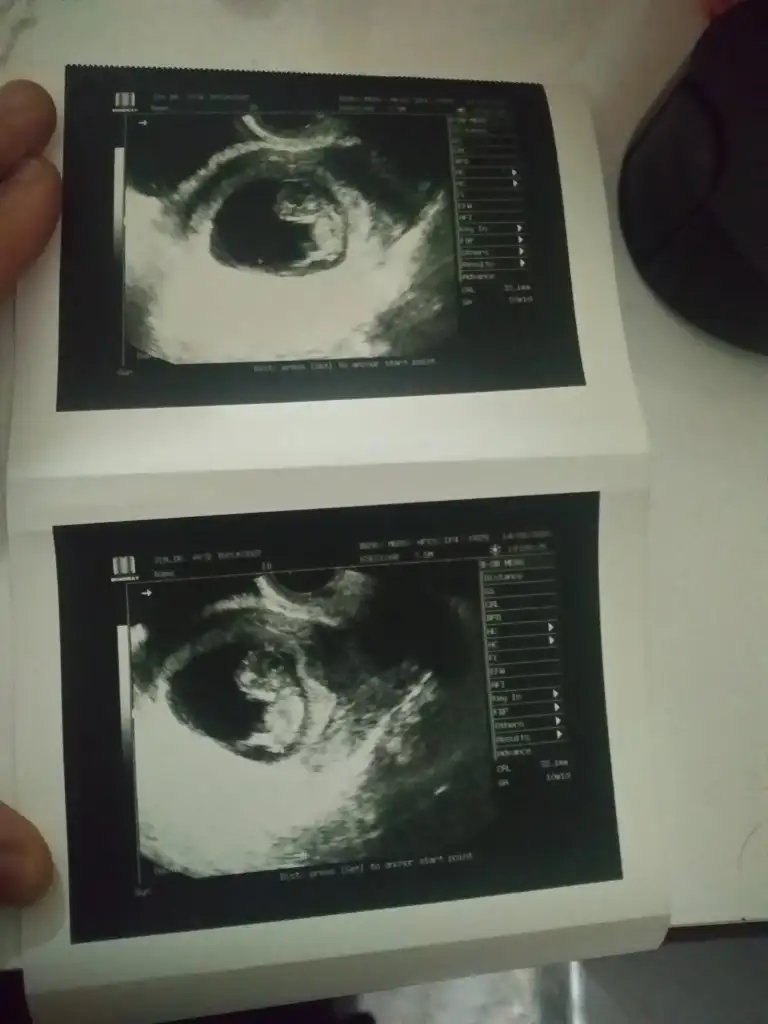

MaşallahBende doktordan geldim şimdi ☺ İkili test için haftaya gel dedi, bebek 4,9cm olmuş 5 olsa daha iyi dedi, folikasit prilam tüm ilaçları kesti çünkü karaciğer enzimim yüksek çıkmış haftaya tekrar bakılacak prilamsız nasıl yaşıycam hiç bilmiyorumkalp atışı iyi dedi çok şükür cinsiyeti 16da söyliycem dedi sizden tahmin bekliyorum

Eki Görüntüle 2590492